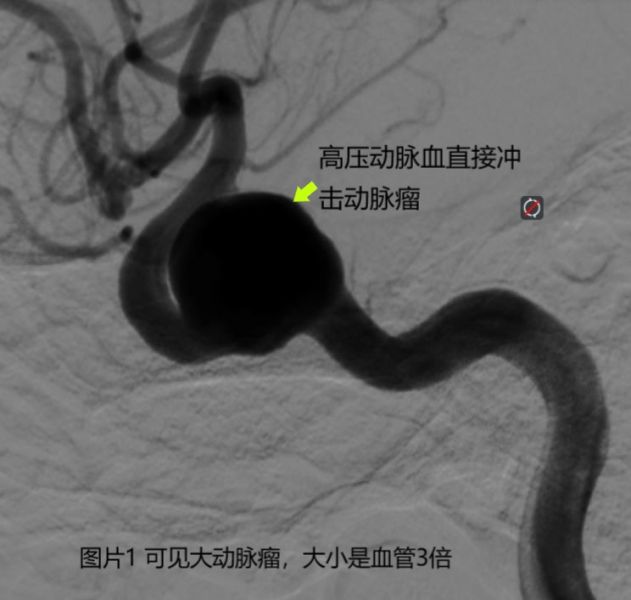

神经内科大主任、神经内科一病区主任黄天清高度重视,组织全科讨论,认真分析后,考虑头痛与右侧颈内动脉海绵窦段的大动脉瘤有密切的关系。与家属仔细商议病情后,入院后次日就由田勇副主任和梁承财主治医生完成了选择性全脑血管造影术,术中确定“空泡样”病变是右侧颈内动脉上的一个大动脉瘤(见图片1)。该动脉瘤大小有1.5公分,而生长该动脉瘤的血管大小只有0.5公分,动脉瘤大小竟然是血管大小的3倍,像一个吹胀了的“气球”。